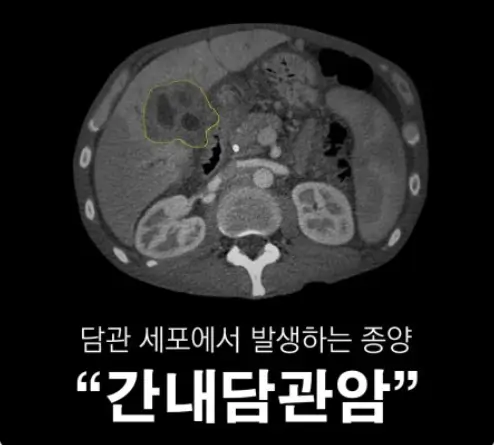

담관세포암은 담도 내부의 담관상피에서 발생하는 간암의 한 종류입니다. 췌장암은 미디어를 통해서 자주 접해 익숙하게 알고 있지만 담도암과 담도에 관한 내용은 잘 모르시는 분들이 많으십니다. 담도는 간에서 생성된 담즙을 저장하고 소장으로 전달하는 역할을 하며 이곳에 암이 발생하는걸 담관세포암(담도세포암)이라고 합니다. 담관세포 안의 증상과 진단하는 법, 치료방법에 대해 알아봅시다.

- 컴퓨터 단층촬영(CT) 스캔: CT 스캔은 명확한 이미지를 제공하며 종양의 크기, 위치 및 다른 곳으로의 암의 이전등을 평가하는 데 사용됩니다.